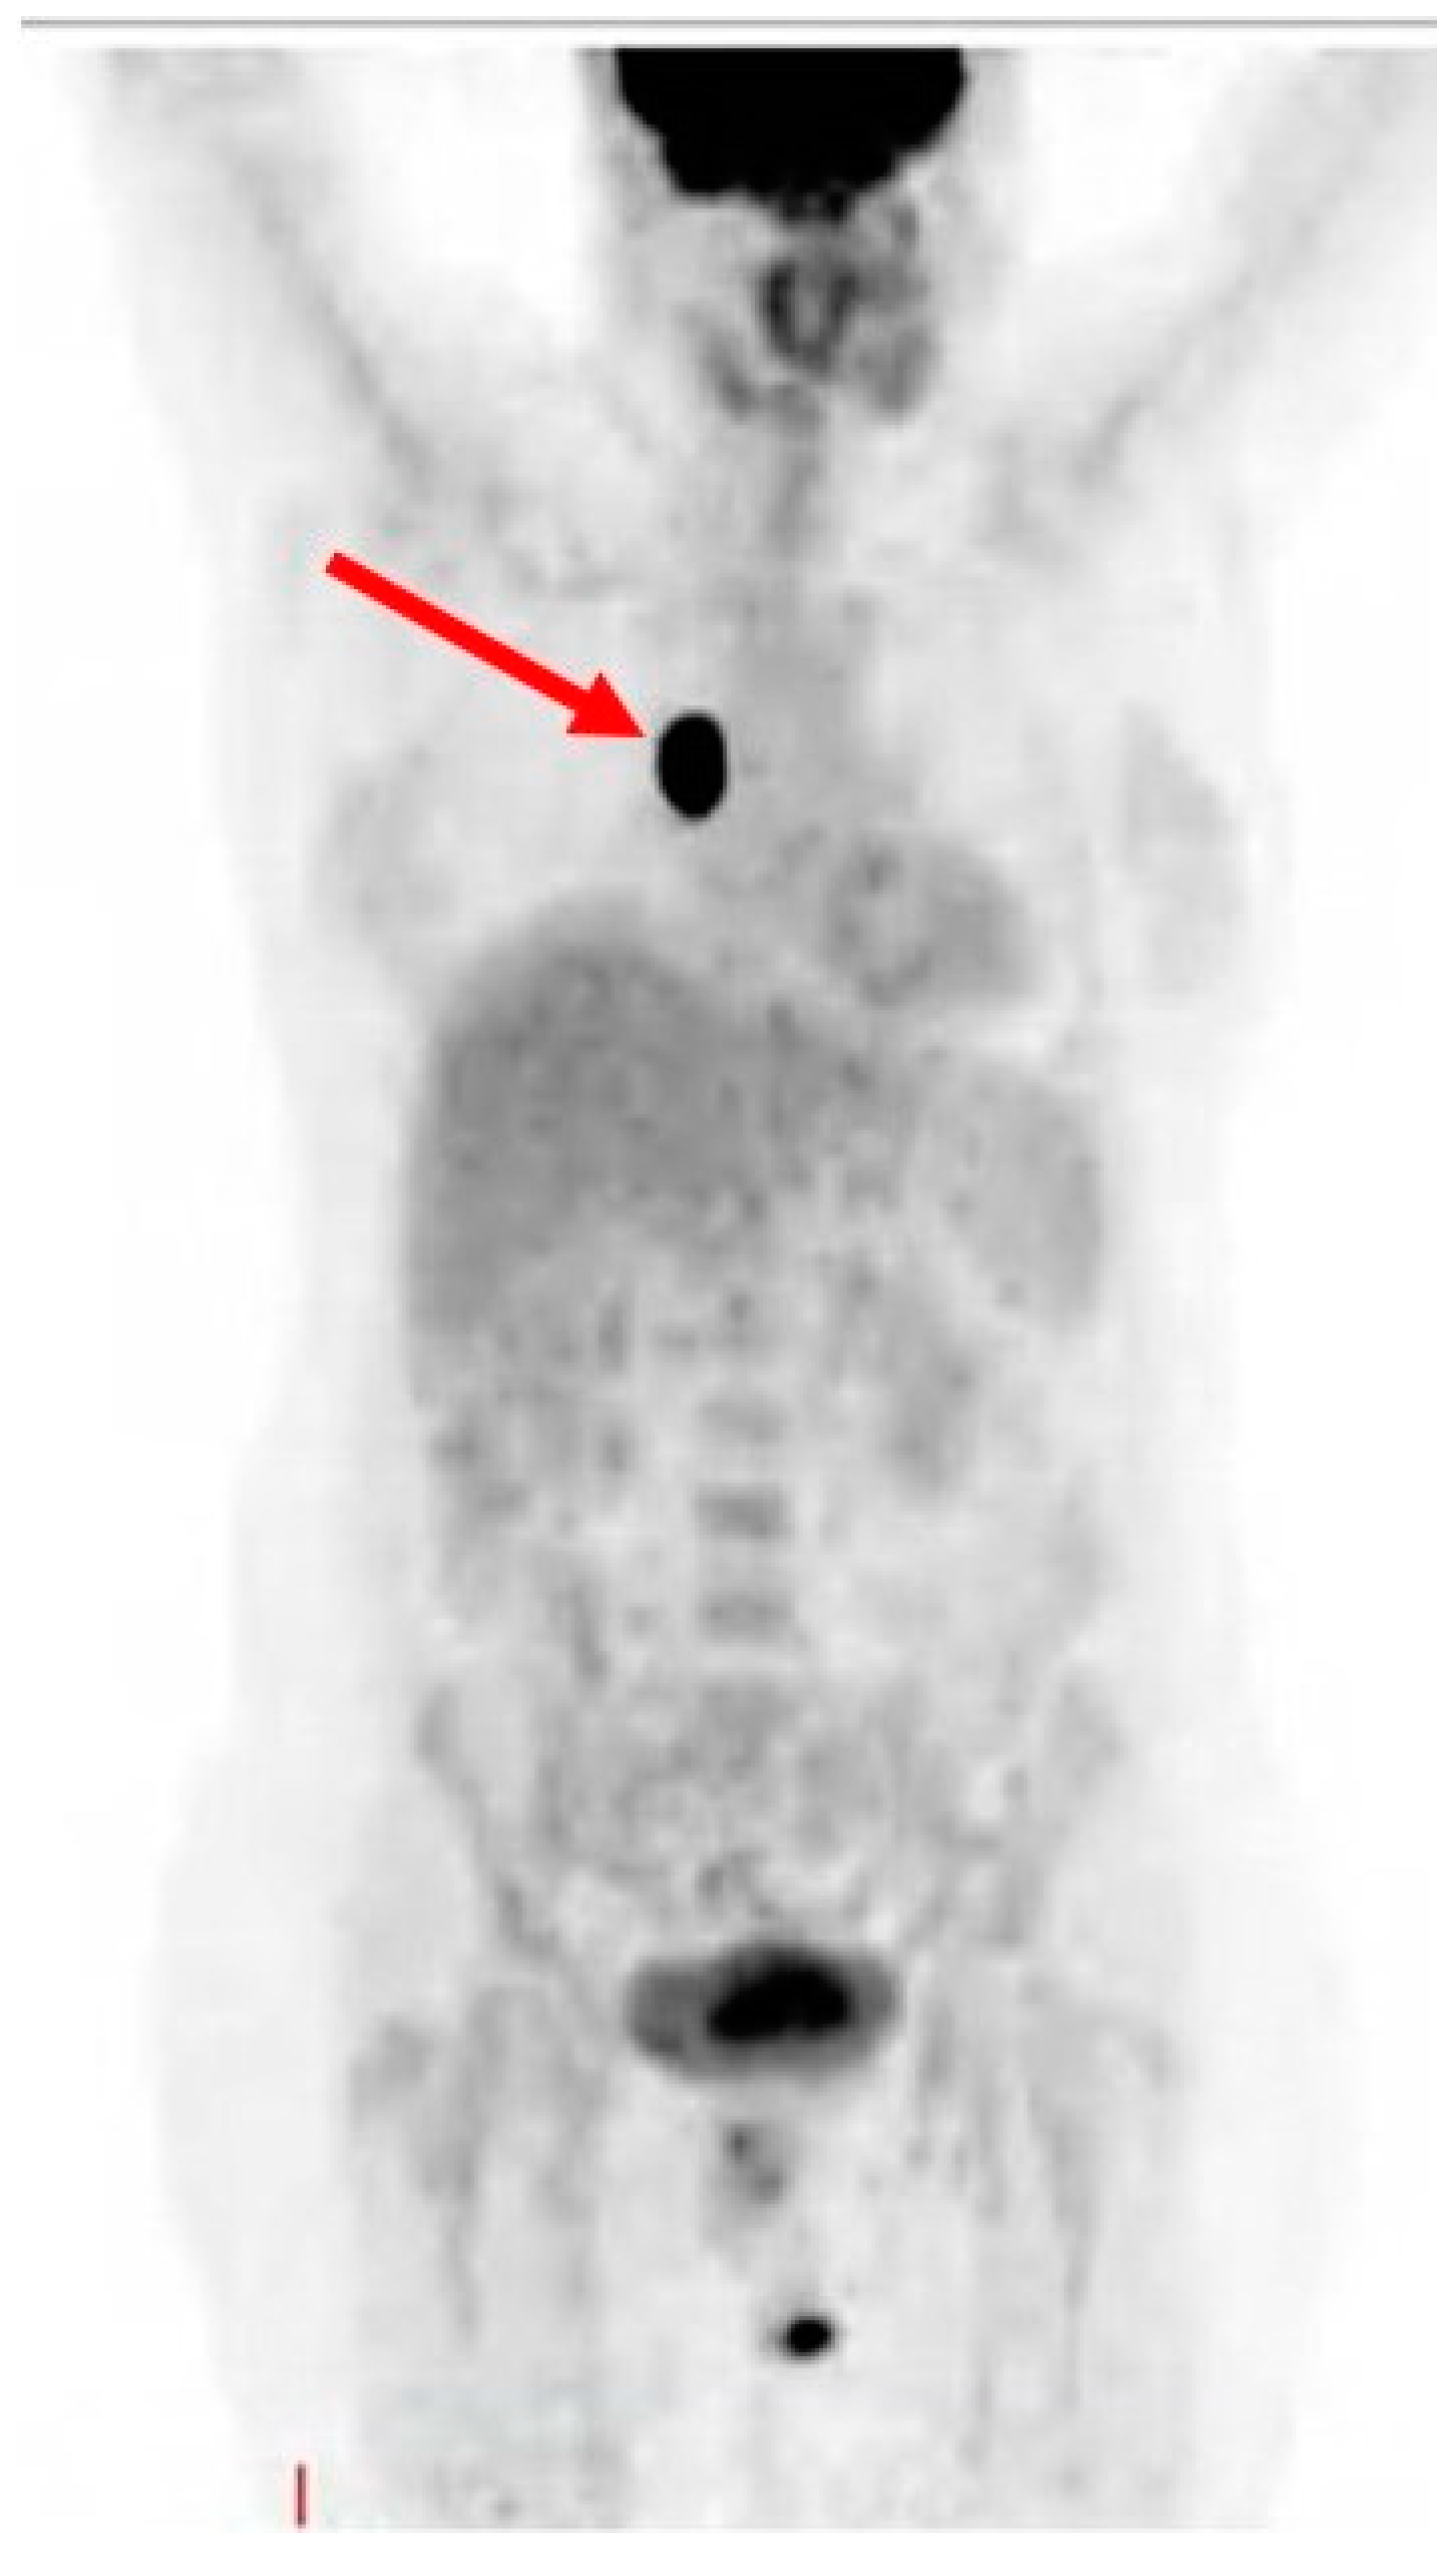

On August 2018, a PET–CT scan was performed, revealing weak hyper metabolic absorption in soft tissue in the area of the nevus. A multidisciplinary team excised the nevus and continuously monitored the patient.

In September 2018, a wide excision of the primary tumor was performed. Two months’ post-surgery, a follow-up PET–CT scan revealed no evidence of disease and the patient underwent regular monitoring by a cardiologist, oncologist, and immunologist, including monthly cardiac MRI and Echo as well as blood tests for troponin and pro-BNP.

Figure 4. PET–CT scan showing no evidence of disease.